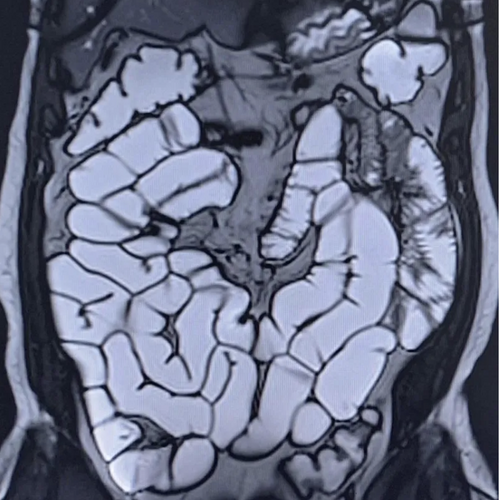

Inflammatory bowel disease

Motilent is transforming how IBD is measured, monitored, and understood - across clinical care, research, and patient engagement.